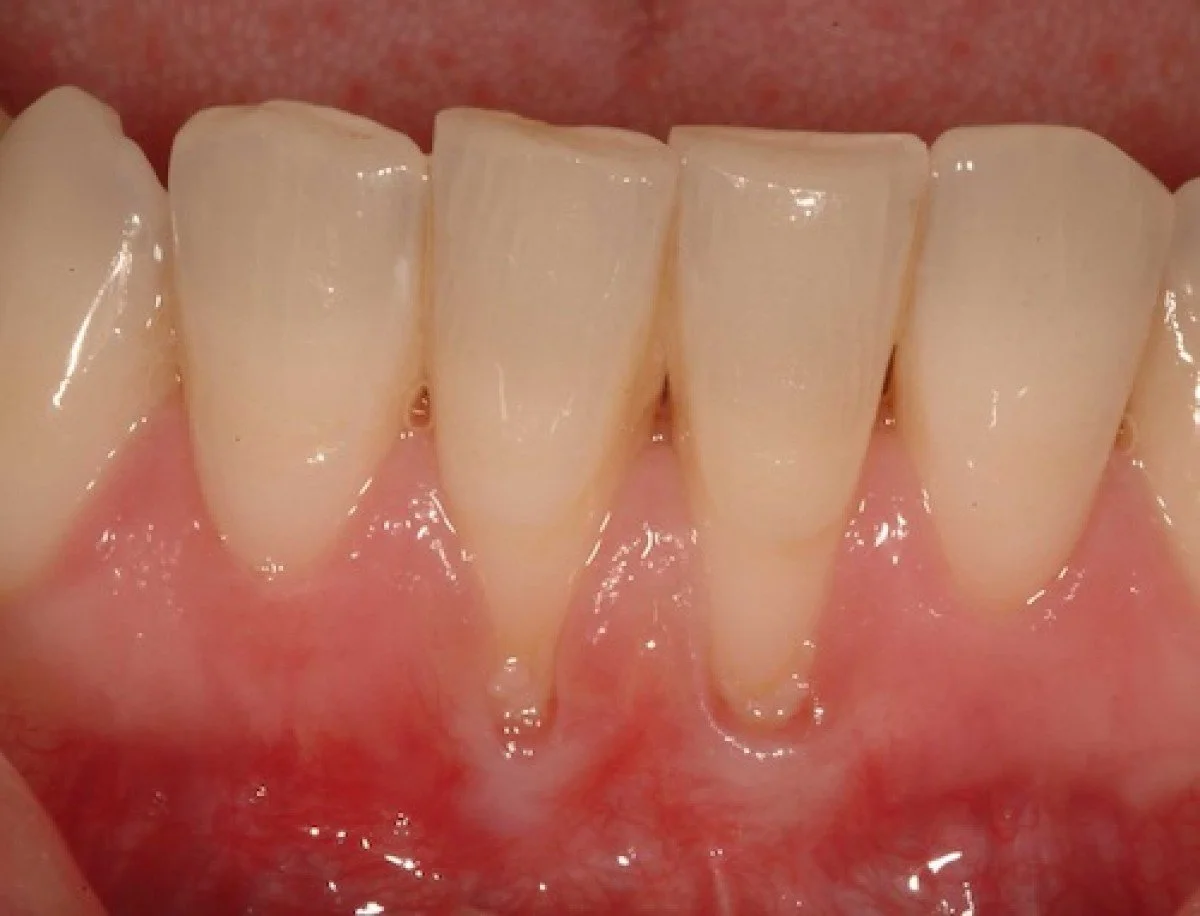

Tooth recession, clinically referred to as gingival recession, is the process whereby the gum tissue surrounding the teeth wears away or retracts, exposing more of tooth surface or its root. This condition can be a precursor to other dental issues, such as tooth sensitivity, decay, and even tooth loss if left untreated.

The primary causes of gingival recession include periodontal disease, which encompasses a range of inflammatory conditions affecting the supporting structures of the teeth. Chronic periodontitis, a more advanced form, leads to the destruction of gum tissue and alveolar bone, contributing significantly to recession. Other contributory factors include aggressive tooth brushing, which can abrade the gingival tissue, and malocclusion, where misaligned teeth cause abnormal forces and stress on the gums. Additionally, habits such as tobacco use and bruxism (teeth grinding) exacerbate gum wear and recession.